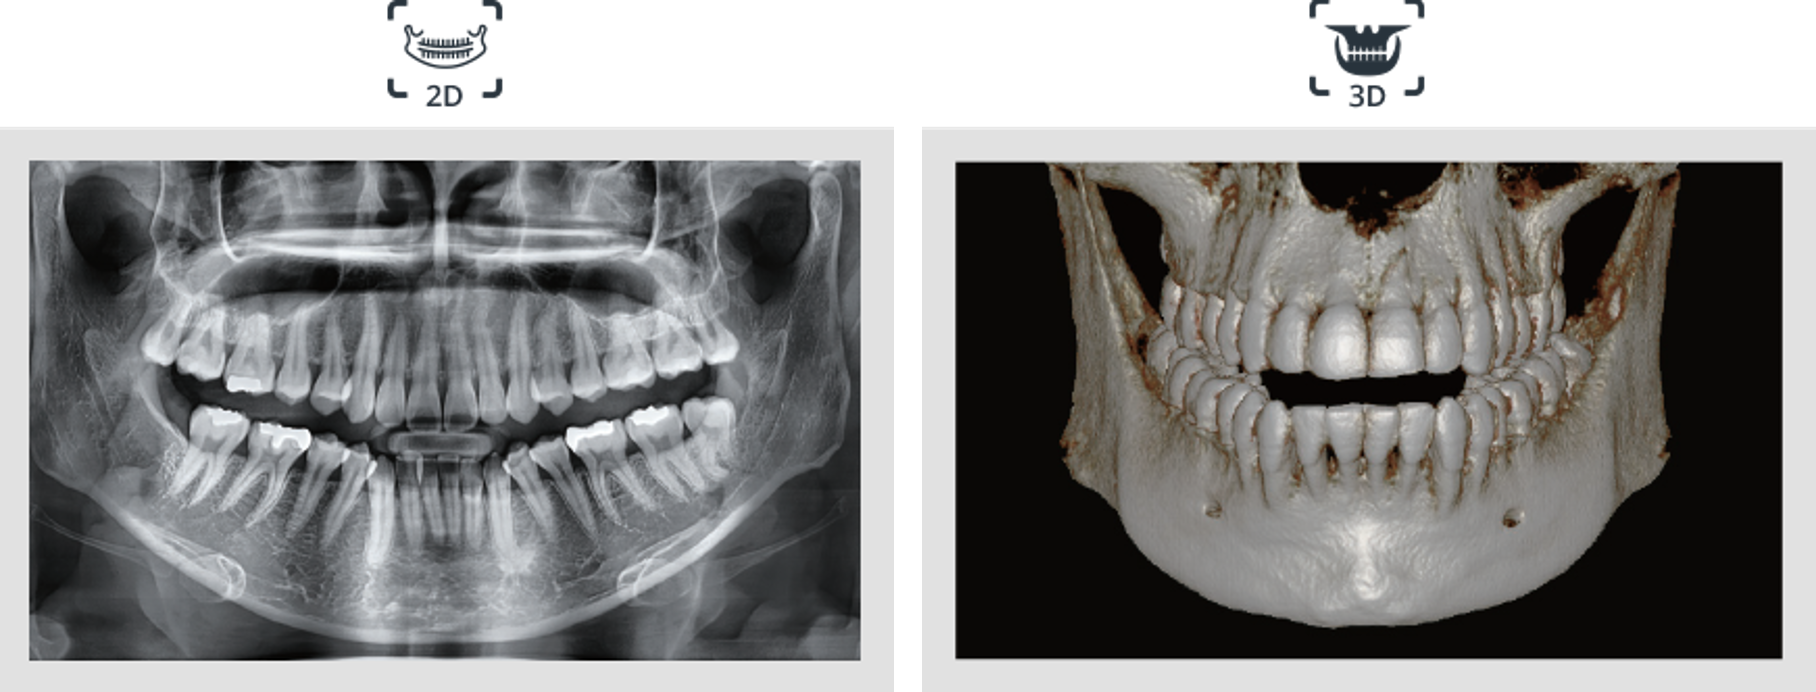

2D Y 3D EN UN VISOR

La visualización de imágenes 2D y 3D juntas proporcionan muchos beneficios. No es necesario utilizar dos programas de software diferentes y la función de un visor representa un aspecto profesional para sus pacientes.

Este diseño ayuda a los pacientes a comprender mejor las imágenes, lo que eventualmente dará como resultado un aumento de aceptación.